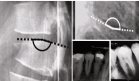

Esta última reveló un sistema coronario derecho dominante, sin lesiones ateroscleróticas obstructivas y una fístula coronaria originada en la porción distal de la arteria descendente anterior, con drenaje hacia el ventrículo izquierdo.

Las imágenes angiográficas mostraron claramente la extravasación del medio de contraste desde la arteria hacia la cavidad ventricular (figuras 2 y 3), lo cual explicaba la sintomatología del paciente.